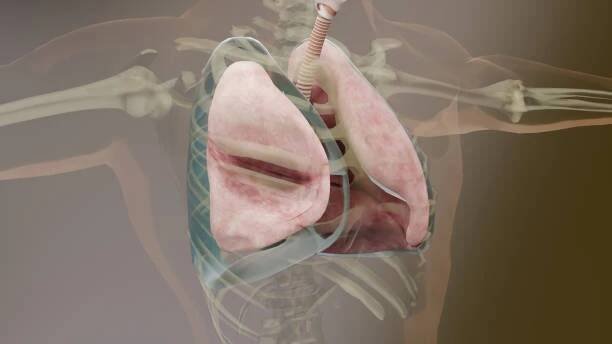

3d ilustrace pneumotoraxu, normální plíce versus zhroucené, příznaky pneumotoraxu, pleurální výpotek, empyém, komplikace po poranění hrudníku, vzduch v pleurálním prostoru, 3d render - pleural cavity - stock snímky, obrázky a fotky